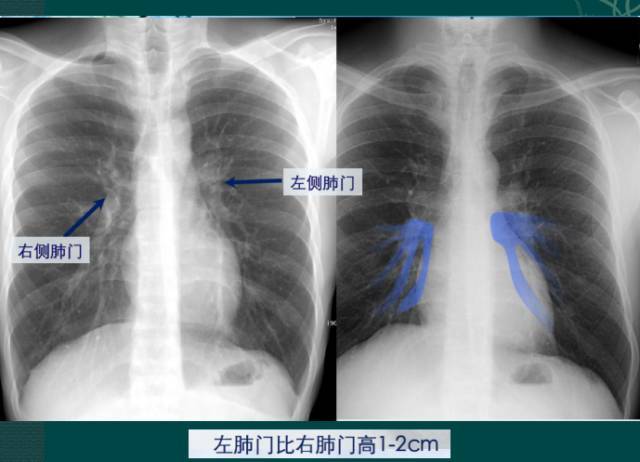

一文看懂胸片